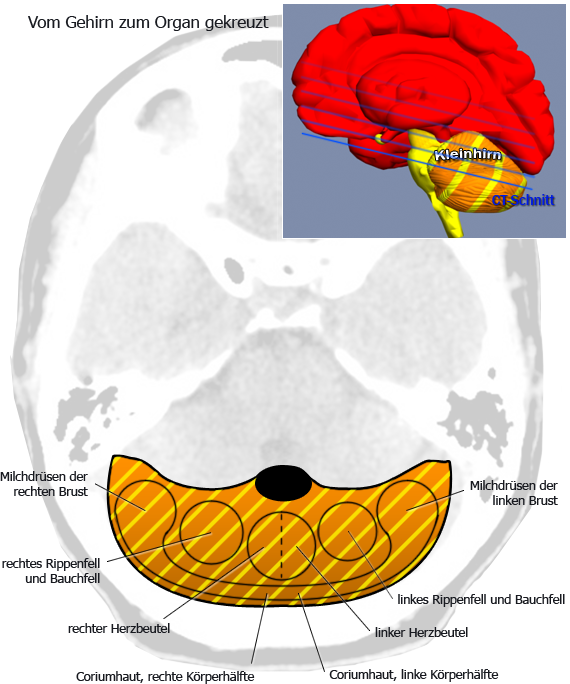

Kleinhirn: